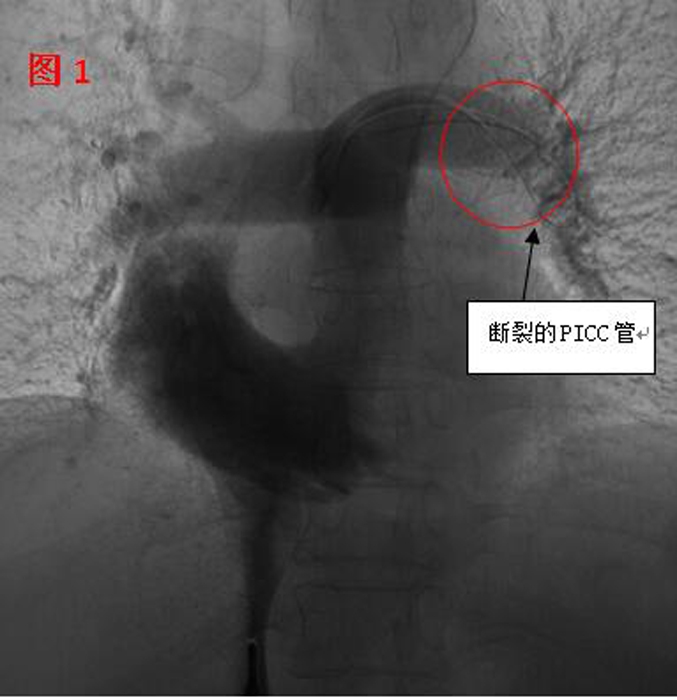

??? 11月2日,在醫(yī)院多個(gè)科室的配合下,這臺(tái)心臟異物取出術(shù)開始了。血管外科醫(yī)生在手術(shù)時(shí)發(fā)現(xiàn),斷裂的PICC管竟完全移位至病人的心室、肺動(dòng)脈(見圖1),情況十分棘手。術(shù)中應(yīng)用異物捕捉系統(tǒng)時(shí),由于導(dǎo)管隨心臟跳動(dòng)和呼吸的影響,擺動(dòng)巨大,捕捉后導(dǎo)管反復(fù)滑脫,且術(shù)中患者心臟稍受刺激就會(huì)出現(xiàn)心律失常。